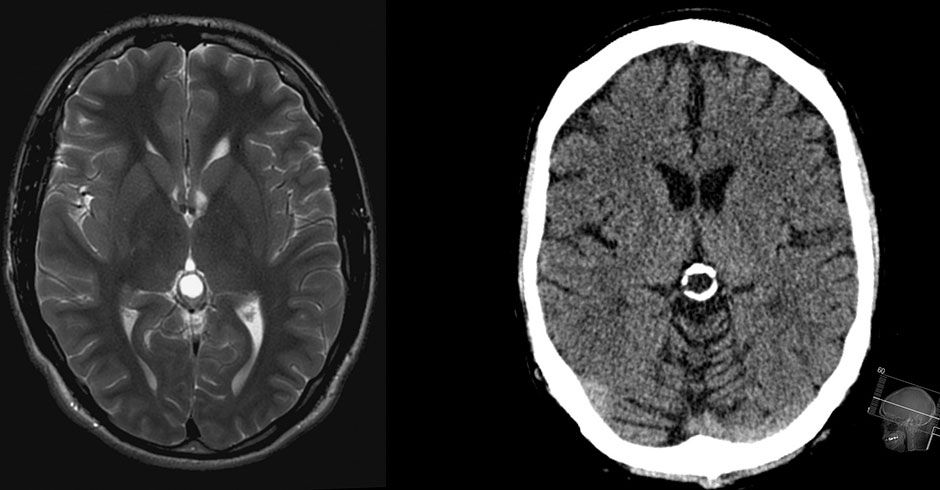

Beyin zarı 3 katmanlıdır. Bu zarlar arasında beyin boşlukları vardır. Bazen bu boşluklarda normalden aşırı genişlemeler olabilir. Pineal bölge kistleri de bu boşluklarda gelişen genellikle iyi huylu olan kistlerdir. İnsanların büyük bir kısmında tesadüfen rastlanabilir. Bu bez üzerinde gelişen Pineal Kistler; çeşitli çaplarda olabilirler. 0,5 cm ye kadar olanlar herhangi bir bulgu vermezler. 0,5 cm den büyük olanları takibe almak gerekir. 6 ay ve 1 yıl sonra MR kontrolü önerilir. Biyokimyasal tanı yöntemleri; tümör belirteçleri malign germ hücre elemanlarının taramasında faydalıdır. Alfa fetoprotein ve beta-HCG rutinde kullanılan belirteçlerdir. Kan ve BOS’ta artmış olarak bulunması anlamlıdır.

Semptomlar üç mekanizma ile meydana gelmektedir. Artmış intrakranial basınca sebep olan hidrosefali, direkt beyine ve serebellar kompresyon, endokrin disfonksiyondur. Kist, beyin sıvısının geçiş yollarını tıkayarak Hidrosefali dediğimiz beyin suyunun artmasına neden olabilir. Başağrısı, nöbet geçirme, görme bozuklukları, ışığa aşırı duyarlılık şikâyetler olursa doktora başvurmak gerekir.

Eğer sıvı toplanmasına (hidrosefali) neden olmamış ise tedavisine gerek yoktur. Eğer hidrosefaliye neden olmuşsa cerrahi olarak tedavi etmek gerekir.